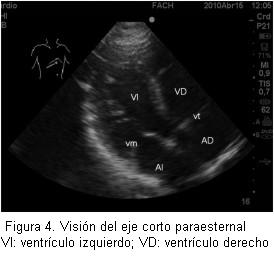

Los resultados de este taller demuestran claramente que se cumplió con el objetivo planteado al inicio: enseñar los principios básicos de ecografía transtorácica y ecografía para punción vascular. Esto se evidenció en la clara mejoría de los resultados de la prueba aplicada antes y después del taller (figura 3). Así con la realización de una introducción teórica y estaciones prácticas (figuras 4 y 5) se logra un significativo avance en la comprensión de la ecografía por parte de los anestesiólogos.

Se ha planteado que el examen ecocardiográfico transtorácico que realiza un anestesiólogo es completamente diferente al examen que realiza el cardiólogo y, por supuesto, no pretende de manera alguna reemplazarlo. Esto se explica porque el anestesiólogo busca resolver preguntas concretas con respecto a lo que ocurre con el corazón en el paciente en su perioperatorio: el estado de la volemia, la contractilidad y tamaño de las cavidades cardíacas. Existen varias publicaciones que avalan la utilidad de la ecocardiografía para los anestesiólogos. Uno de los primeros estudios fue hecho por el grupo de Sloth (6), que evaluaron a pacientes hemodinámicamente inestables en su postoperatorio y obtuvo imágenes satisfactorias por encima del 80% de los casos e imágenes que fueron útiles como guía y manejo de estos pacientes. Durante el preoperatorio se ha planteado la gran utilidad que puede tener la ecocardiografía para evaluar pacientes con presencia de soplos en el examen físico, con capacidad funcional no evaluable y aquellos pacientes con severa alteración de sus capacidades mentales (enfermedad de Alzheimer, deterioro senil) (7). En el intraoperatorio realmente puede ser útil para la monitorización del estado hemodinámico de manera no invasiva (8,9), que permite realizar nuevos diagnósticos, iniciar nuevas terapias y reemplazar otras formas de monitorización, como línea arterial o catéter venoso central. Otra indicación que puede resultar muy interesante es la alta utilidad que puede tener la ecografía durante las maniobras de resucitación cardiopulmonar, ya que en períodos muy breves de detención de las maniobras de masaje cardíaco externo, es posible visualizar a través de la ventana subcostal qué sucede realmente con el miocardio, y es así que se ha demostrado que no siempre el diagnóstico de actividad eléctrica sin pulso corresponde a esta entidad (10).

Las principales críticas al taller fueron la falta de claridad al explicar el tipo de transductor que debe utilizarse para cada procedimiento. Así, para realizar ecocardiografía transtorácica, se requiere de un transductor que alcance planos más profundos y por esto se utiliza uno cardiológico con frecuencias de 5 MHz. Para realizar punciones vasculares se requiere de un transductor lineal que tenga gran precisión y no es necesario que alcance grandes profundidades, por esto se utiliza un transductor lineal entre 12 y 15 MHz. Este último es el mismo que se utilizaría para una punción de nervio bajo ecocardiografía.

Además, todos los transductores tienen una marca que se correlaciona con la orientación de las imágenes en la pantalla. Se puede trabajar con diferentes angulaciones del transductor a 0°, 90° y todos los valores intermedios. También se puede realizar movimiento de “tilting” o balanceo que permite efectuar un barrido de las estructuras.